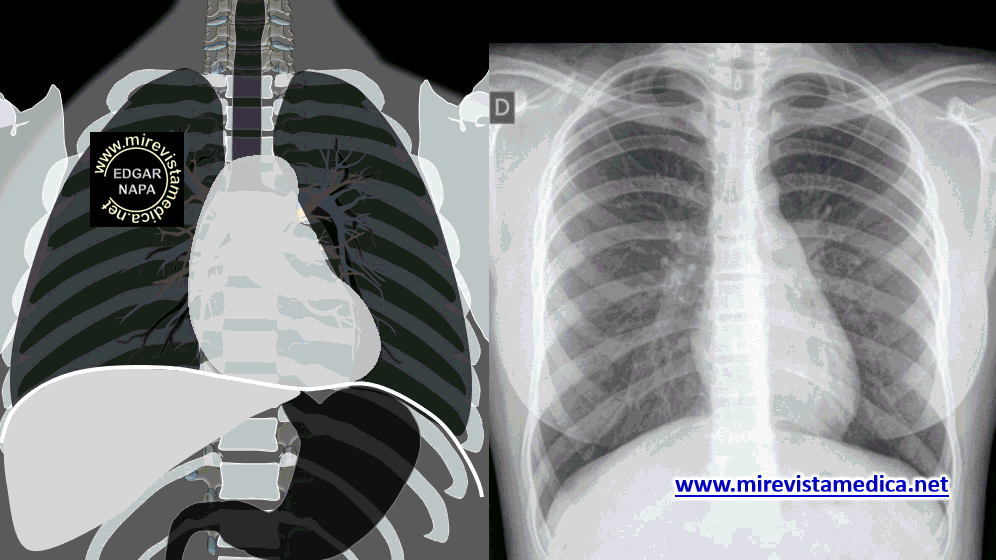

Lóbulo pulmonar secundario - patrones

Descripción resumida y concisa de anatomía humana y patologías con esquemas, dibujos e imágenes dinámicas (Gifs) además del apoyo de imágenes radiográficas, de ultrasonido y tomografía computarizada para su mejor comprensión.